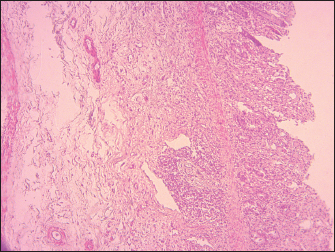

The most important histopathological lesions were observed in the lungs, intestines, spleen, and lymph nodes. The lungs had the most severe histopathological abnormalities, which were characterized by edema in the alveoli combined with fibrinous exudate infiltration of mononuclear cells and thickening of the interalveolar septa (Fig. 5), presence of syncytial cells (Fig. 5). Intestines revealed ulcerations of the intestinal mucosa in some areas, loss of intestinal villi with the intestinal crypts appearing clear and loss of epithelium, the lamina propria was infiltrated with Macrophages and lymphocytes, the duodenum, jejunum, and ileum showed extensive effusion of the submucosa with progressive thickening of the submucosal layer (Fig. 6). Degeneration and necrosis of glandular epithelial cells were also seen.

Fig. 5. Pulmonary parenchyma severely infiltrated with inflammatory cells (interstitial pneumonia) with a group of syncycial cells associated with severe bronchiolitis (40X, H&E).

Our study revealed the presence of severe broncho-pneumonia, characterized by thickening of the interalveolar septa and the presence of syncytial cells. These findings can be attributed to the extensive replication of the virus in the respiratory epithelium. The thickening of the alveolar septa indicates substantial tissue damage, which is likely attributable to direct viral cytopathic effects and the host’s immune response. Such damage may impair gas exchange, potentially leading to respiratory distress and in more severe cases, hypoxemia and death. PPRV is known to produce syncytia (fusion of cells) in Vero cells, a cell line derived from African green monkey kidney epithelial cells (Osman et al., 2019). Macroscopic findings of the lungs, trachea, and small intestine found in this study are mostly similar to those observed in previous studies reported by Begum et al. (2021) and Maina et al. (2015) in experimentally infected goats and sheep and Ugochukwu et al. (2019) in naturally infected sheep and goats.